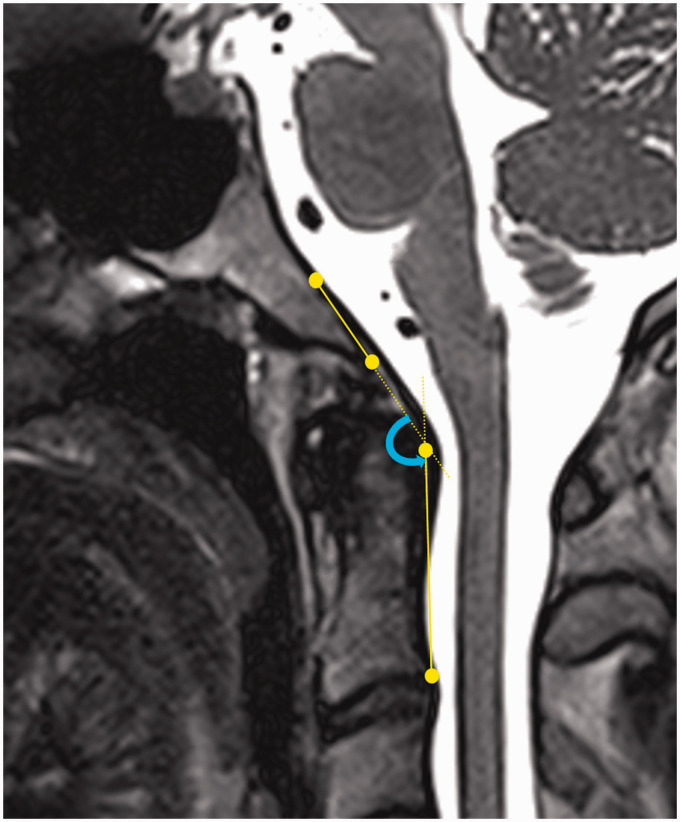

Clivo-axial angle(clivo-cervical angle) 150가 정상. 130도 이하는 심한 뇌간압박 초래.. --> 자율신경이상, 경동맥-미주신경압박이 될수 있다!!